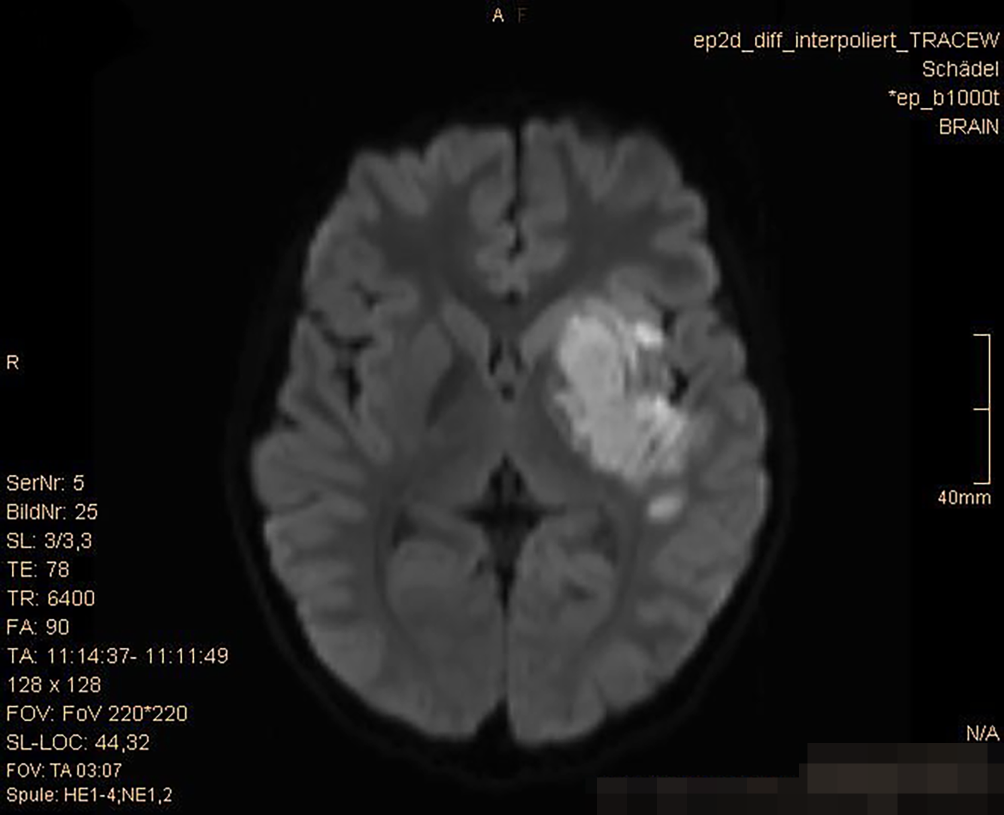

In der durchgeführten kranialen MRT (cMRT) zeigt sich eine nichtdemarkierte Diffusionsstörung im Mediastromgebiet links, genauer im Bereich der Basalganglien links mit Beteiligung der Inselrinde, ohne Nachweis eines Gefäßverschlusses oder -dissektion (Abb. 1 und 2).

Abb. 1

Axiale DWI-MRT (b1000) mit Bild einer Diffusionsrestriktion in den Basalganglien und der Inselrinde der linken Seite

Es wird die Diagnose eines kindlichen Schlaganfalls gestellt; weitere Differentialdiagnosen sind in Tab. 1 angeführt. Eine in der cMRT gezeigte Diffusionsrestriktion im Mediaversorgungsgebiet links erhärtet die Diagnose. Es wird im intensivmedizinischen Setting eine systemische Lysetherapie mit Alteplase (Actilyse®) in der Dosierung 0,9 mg/kg innerhalb eines Zeitfensters von 02:55 h nach Symptombeginn durchgeführt. In stabilem Allgemeinzustand kann der Patient in weiterer Folge am vierten Tag mit schlaffer Hemiparese und zentraler Fazialisparese rechts unter laufender kontinuierlicher Heparintherapie in der Dosierung 15 IE/kg/h mit einer Ziel-PTT im Normbereich zur Vorbeugung eines Rebound-Phänomens nach erfolgter Lysetherapie auf die Normalstation verlegt werden. Die cMRT am 7. Tag nach Symptombeginn mit Gefäßdarstellung zeigt Kaliberirregularitäten teilweise mit Stenosierungen im Bereich der distalen Arteria carotis interna, im A1-Segment der A. cerebri anterior sowie im M1-Segment der A. cerebri media links. Die rechts- und einseitige klinische Präsentation des Schlaganfalls, die fehlenden Entzündungszeichen, ein erhöhtes von-Willebrand-Antigen als Zeichen der Endothelaktivierung, die unilaterale Gefäßmanifestation sowie die Morphologie der Bildgebung sind somit passend zum Bild einer primären ZNS-Vaskulitis des Kindesalters („childhood primary angiitis of the central nervous system“, cPACNS). Es liegt der Subtyp einer idiopathischen Angiographie-positiven nichtprogredienten Großgefäßvaskulitis vor [24]. Therapeutisch erhält der Patient in weiterer Folge eine Methylprednisolon-Stoßtherapie in der Dosierung 20 mg/kg/Tag für 3 Tage mit anschließender oraler Therapie mit Prednisolon in der Dosierung 2 mg/kg/Tag, welche über 10 Wochen ausgeschlichen wird. Zudem werden eine Thrombozytenaggregationshemmung mit Acetylsalicylsäure 200 mg für 2 Jahre sowie eine Antikoagulation mit Enoxaparin 20 mg für 3 Monate veranlasst [5, 6]. Der Patient kann zur weiterführenden Rehabilitation an ein pädiatrisches Reha-Zentrum verlegt werden.